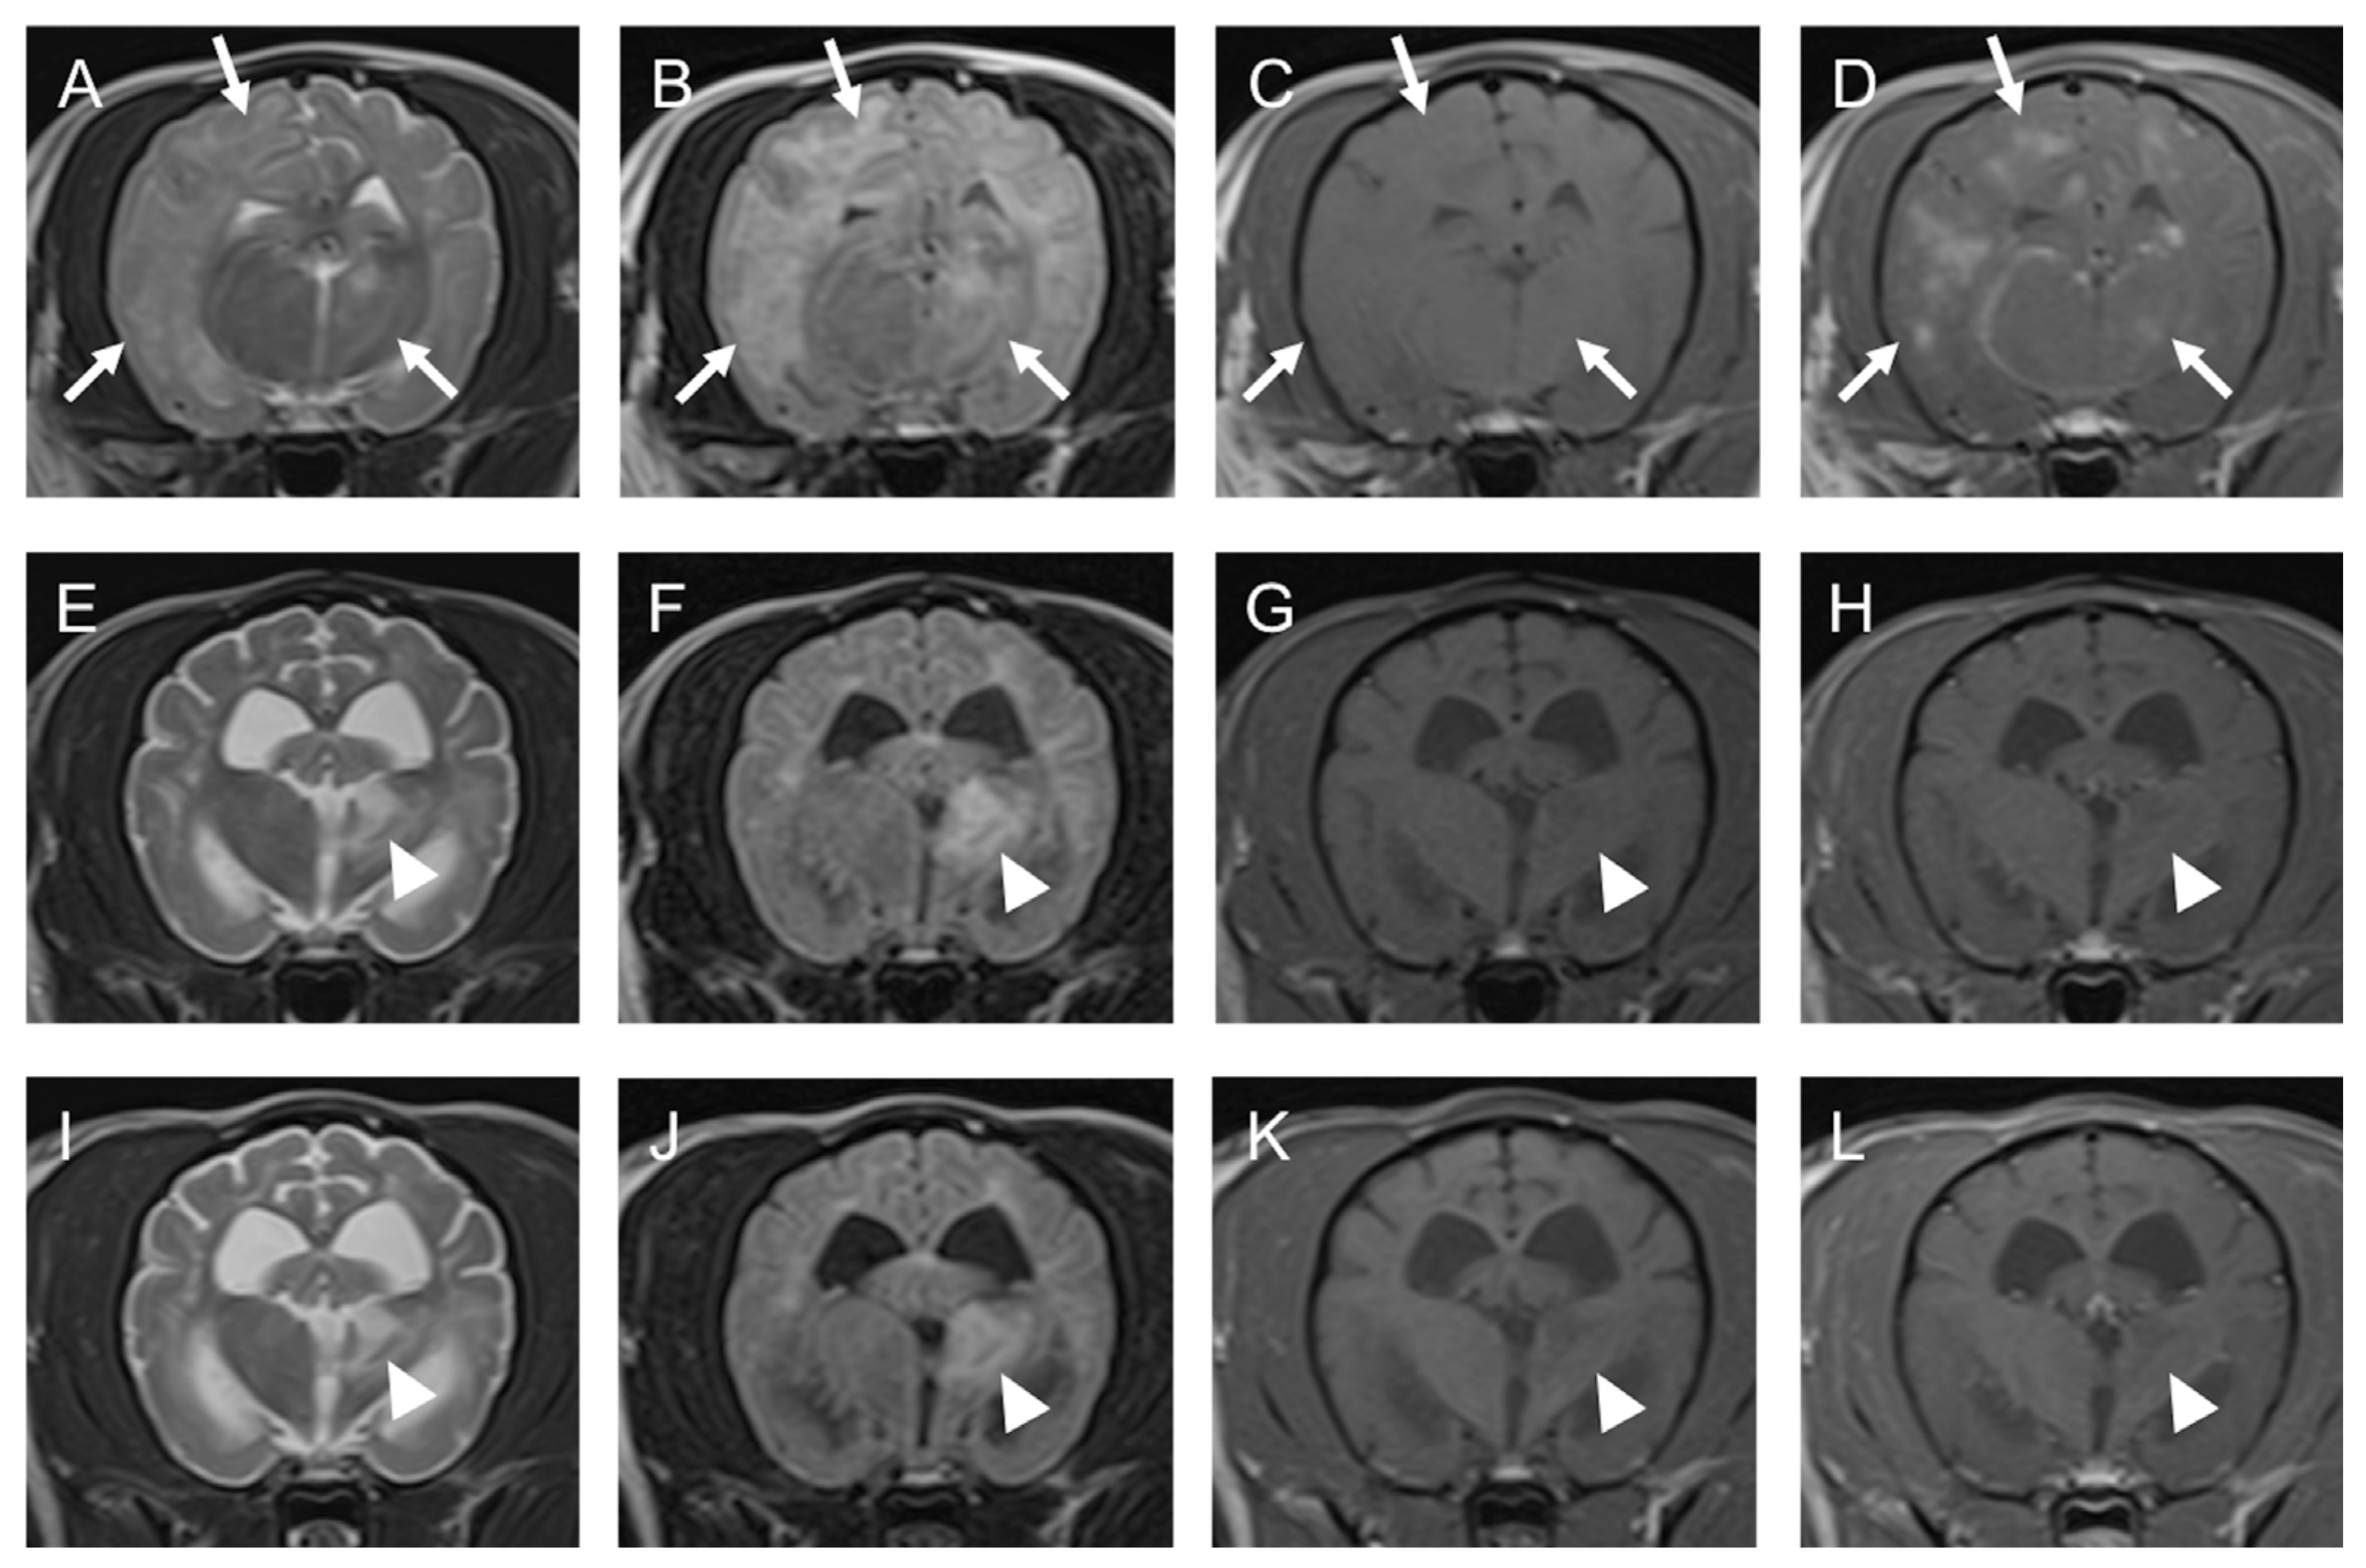

2.1. Case 1

2.2. Case 2